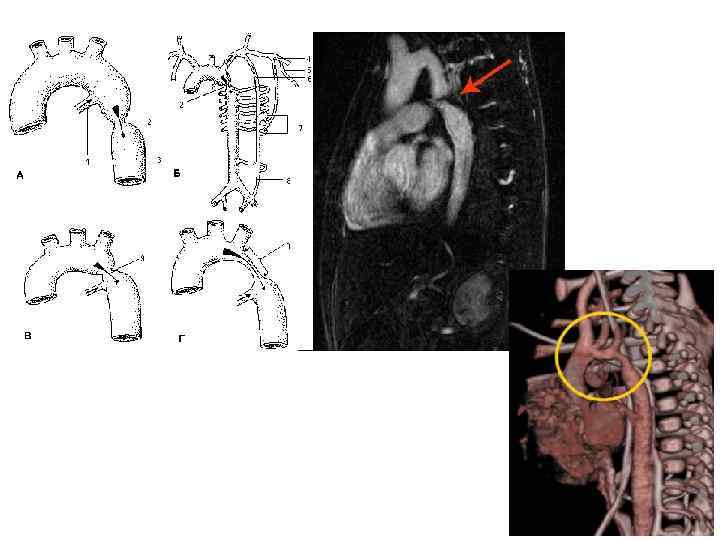

Коарктация аорты • • • врожденный порок к 20— 30 -летнему возрасту у больных развивается стойкая, высокая гипертензия с повышением как систолического, так и диастолического давления хорошо физически развита верхняя половина туловища, полнокровны лицо и шея, в то же время отмечаются гипотрофия и бледность нижних конечностей четко различается величина пульса на руках и ногах, значительно ослаблен пульс на бедренных и подколенных артериях, не определяется пульс на тыльных артериях стоп иногда имеется различие пульса на обеих руках — на правой он больше, на левой — меньше. в норме систолическое давление на ногах выше, чем на руках, на 15— 20 мм рт. ст. , при коарктации аорты все наоборот: на руках АД выше, чем на ногах. при аускультации сердца и сосудов определяется шум изгнания, который лучше всего выслушивается во II—III межреберьях слева от грудины, нередко также и в межлопаточном пространстве. рентгенологически отмечаются выраженная пульсация аорты выше места сужения, постстенотическое расширение аорты, аортальная конфигурация сердца, узурация нижних краев IV—VIII ребер. решающим методом является аортография, которая позволяет уточнить место коарктации и ее протяженность.

Коарктация аорты • • • врожденный порок к 20— 30 -летнему возрасту у больных развивается стойкая, высокая гипертензия с повышением как систолического, так и диастолического давления хорошо физически развита верхняя половина туловища, полнокровны лицо и шея, в то же время отмечаются гипотрофия и бледность нижних конечностей четко различается величина пульса на руках и ногах, значительно ослаблен пульс на бедренных и подколенных артериях, не определяется пульс на тыльных артериях стоп иногда имеется различие пульса на обеих руках — на правой он больше, на левой — меньше. в норме систолическое давление на ногах выше, чем на руках, на 15— 20 мм рт. ст. , при коарктации аорты все наоборот: на руках АД выше, чем на ногах. при аускультации сердца и сосудов определяется шум изгнания, который лучше всего выслушивается во II—III межреберьях слева от грудины, нередко также и в межлопаточном пространстве. рентгенологически отмечаются выраженная пульсация аорты выше места сужения, постстенотическое расширение аорты, аортальная конфигурация сердца, узурация нижних краев IV—VIII ребер. решающим методом является аортография, которая позволяет уточнить место коарктации и ее протяженность.